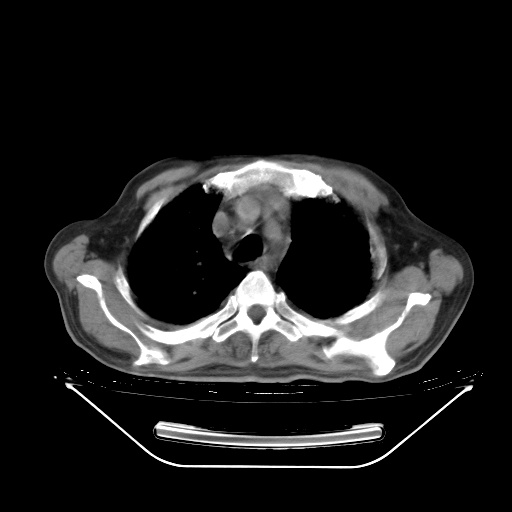

胸腹部CT,诊断意见:左上肺叶钙化灶、左侧胸膜局限性增厚并钙化、胆囊炎。描述部分肺组织呈磨玻璃样改变。